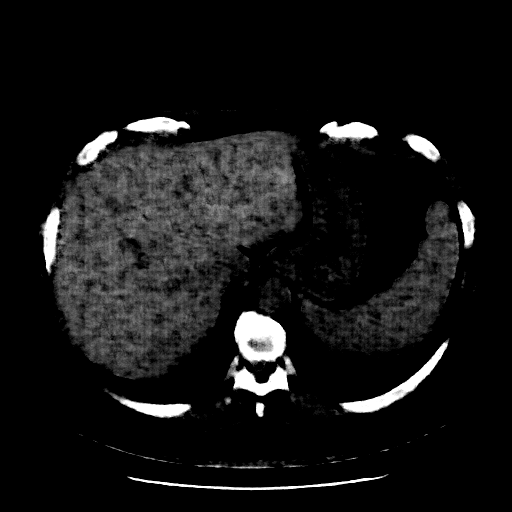

Reconstructed NATIVE CT scan (cycle consistency)

Full window (WL 1023.5, WW 4095 β†’ Low βˆ’1024, High +3071)

Actual HU range: [-1024.0, 544.7]